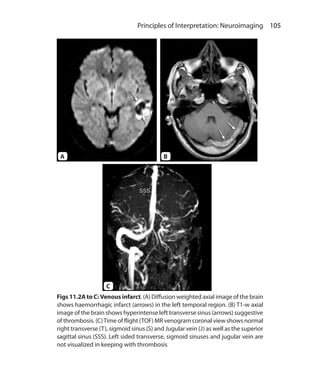

Osteoarthritis 71f

Otologic implants 89

P

Pacemakers 89

Pancreatic duct 186f, 188f

Parallel imaging artifact 83f, 84

Paramagnetic agent 92, 94

Parameters of scanning 18